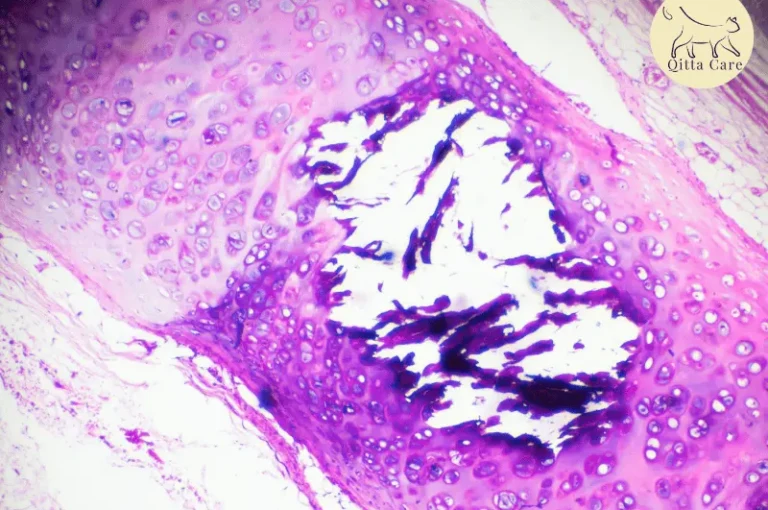

اسباب التهاب الجزء الأمامي من عين القطط وعلاجه

التهاب الجزء الأمامي من عين القطط، بما في ذلك القزحية قد يكون مرتبطًا بالتهاب في الجزء الخلفي من العين، بما في ذلك الشبكية، حيث تحتوي الشبكية على الخلايا الحساسة للضوء (العصي والمخاريط) والخلايا الأخرى التي تحول الصور إلى إشارات وتُرسل ...